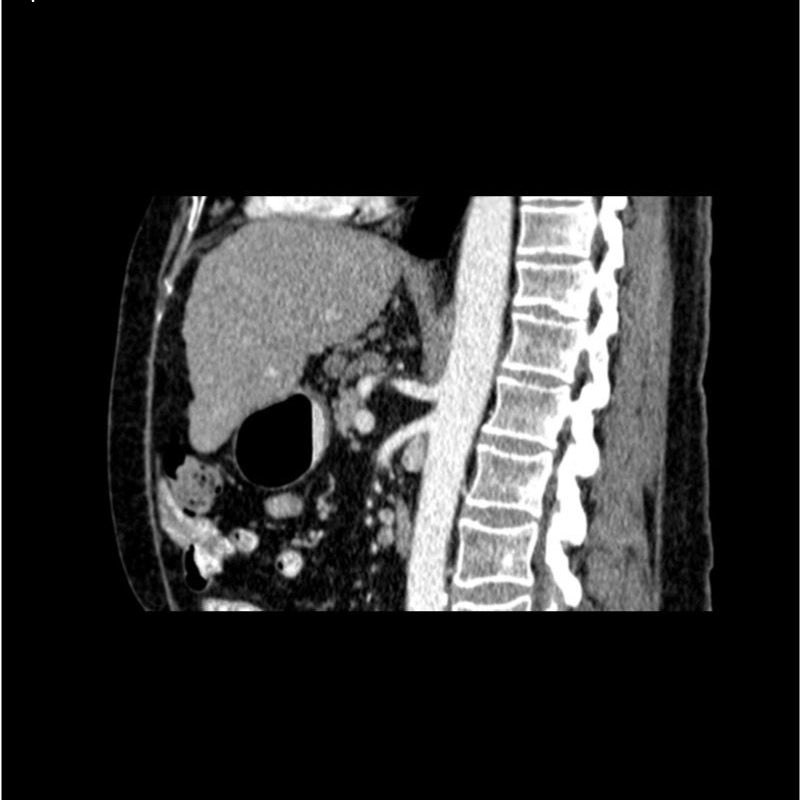

abdomen in portal venous phase. It covers the tenth thoracic vertebra to the third lumbar vertebra. The phantom represents an abdomen after cholecystectomy with small clips. The liver has typical signs of cirrhosis and there is an inferior vena cava filter implanted at the level of the third lumbar vertebra. Both kidneys have cystic lesions and there is a small kidney stone on the left side.

Realistic simulation of vasculature, bone and soft tissues, including the liver, pancreas, spleen, adrenals, kidneys, stomach, small intestine and colon.

- Liver cirrhosis

- cholecystectomy

- inferior vena cava filter

- kidney cysts

- kidney stone

- lymph nodes.